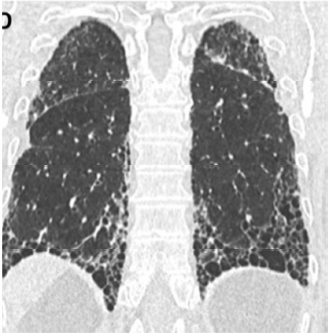

O paciente traz uma tomografia prévia solicitada pelo médico de família e representada nas imagens a seguir.

American Journal of Respiratory and Critical Care Medicine. Volume 198 Number 5 September 1 2018 (com adaptações).